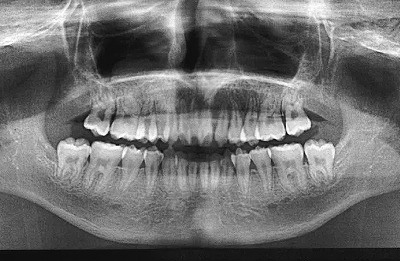

今日のX線を見てわかると思うが、全ての乳歯が永久歯に生え変わっている。

比較に2年前のそれを見てみるとよくわかるだろう。

として、2つのX線像を並べて下さった。

これ、今回。

確かに。

よくわかります。

今回、歯は横一線。

2年前、歯の下に歯がある、乳歯の下の永久歯だ。